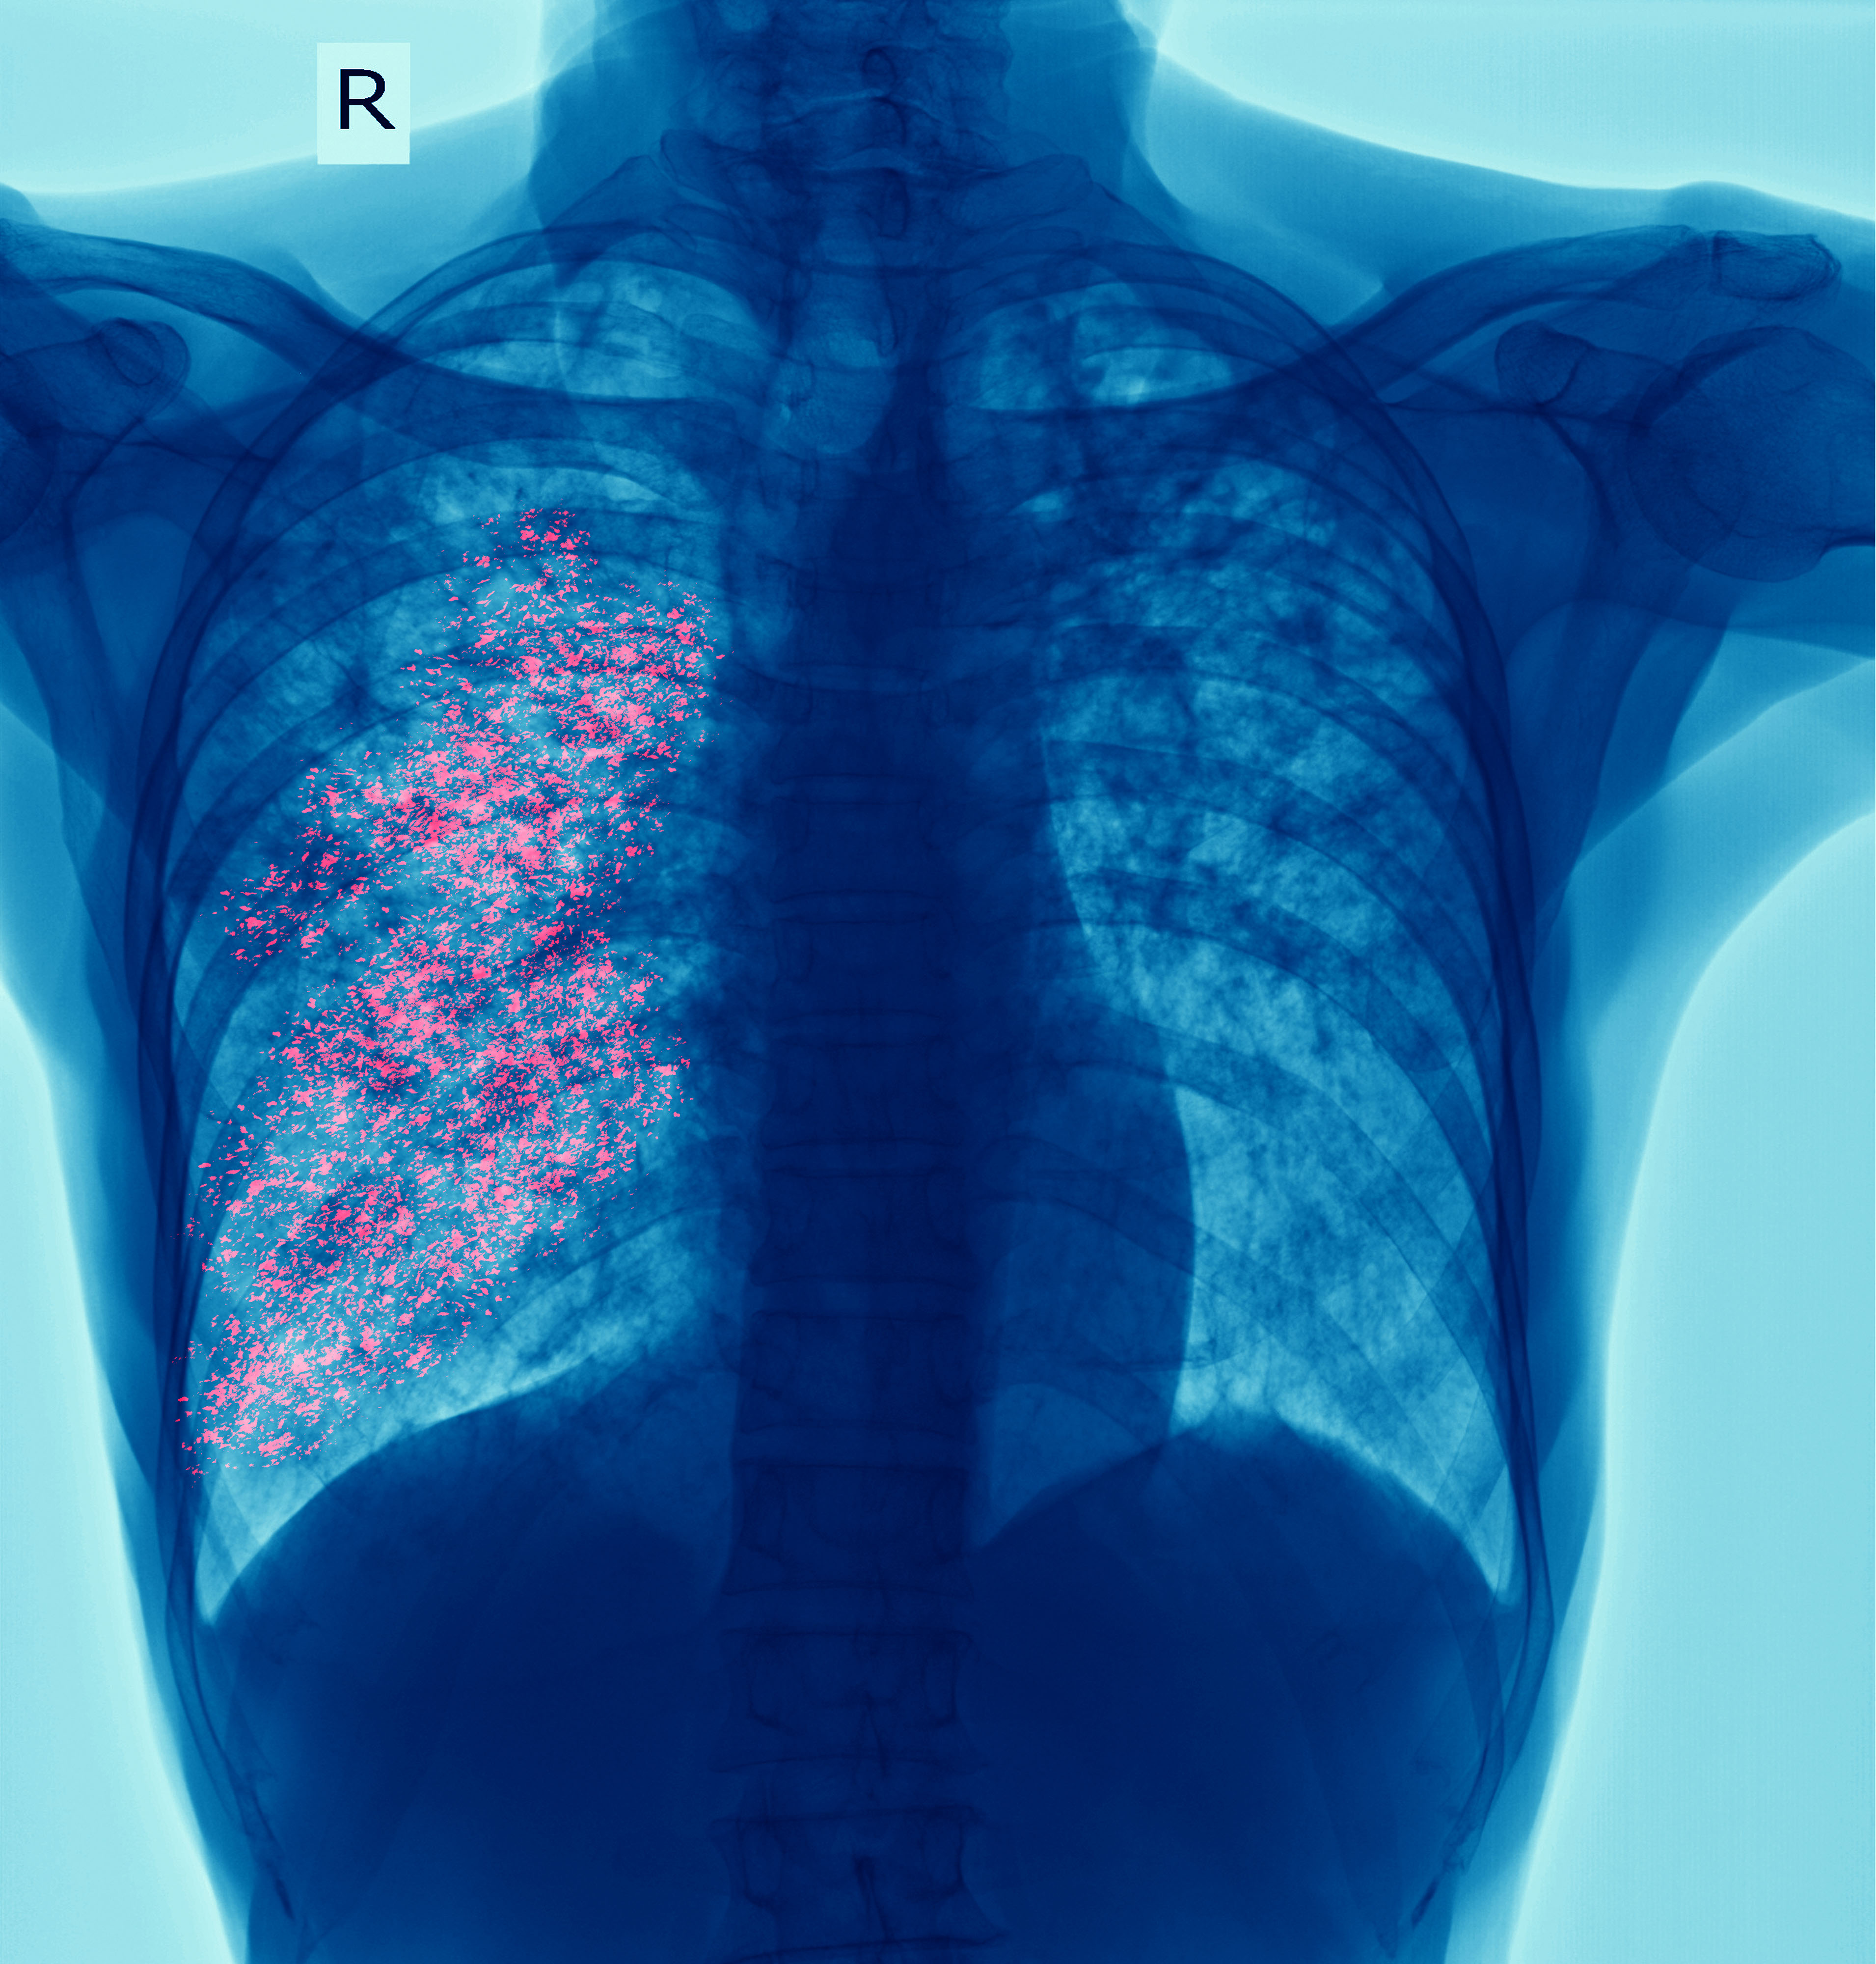

From Embolus to V/Q Mismatch

When a clot lodges in the pulmonary arteries, it instantly cuts off blood flow to regions of lung that remain well-ventilated. Air still enters the alveoli, but oxygen molecules have no red blood cells waiting at the capillaries. This creates dead space ventilation—ventilation without perfusion.

Early gas exchange changes:

The patient’s PaO₂ begins to fall because less blood is participating in oxygen uptake. Meanwhile, PaCO₂ may look deceptively normal, because the patient compensates with tachypnea and high minute ventilation.

EtCO₂ clue:

Because exhaled CO₂ reflects perfused alveoli, and many alveoli are no longer perfused, EtCO₂ drops disproportionately compared to PaCO₂. The widened PaCO₂–EtCO₂ gap is a red flag for dead space [5,6].

Later changes:

Over time, inflammation and reduced surfactant downstream cause alveolar collapse and small pulmonary infarctions. These regions behave more like shunt physiology (perfusion without ventilation), layering hypoxemia on top of dead space [6].

Takeaway: A PE patient can look deceptively “normal” on PaCO₂ early, while their EtCO₂ is already plummeting. This mismatch is one of the earliest physiologic footprints of PE.